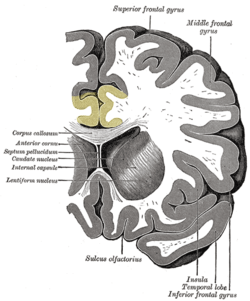

Coronal section of brain. Cingulate cortex is shown in yellow.